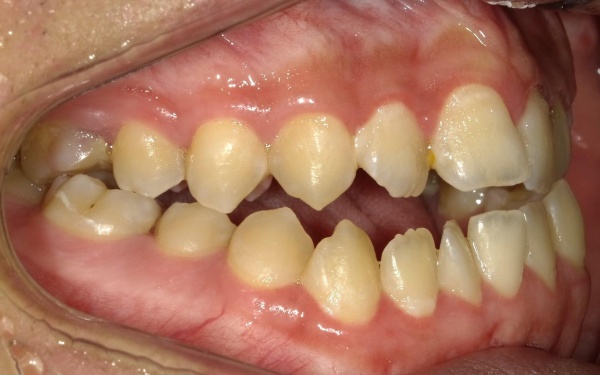

10代男性 顎変形症が原因で下顎がずれて非対称になっていた噛み合わせをサージェリーファースト法を併用した矯正治療で改善した症例

カウンセリング・診断結果 拝見したところ、骨格の問題により下前歯が上前歯より前に出ている前歯部反対咬合と、前歯が開いて噛み合わないオープンバイトが認められました。

さらに、下顎の骨が右方向にずれて上下の歯が噛み合う面が斜めになっていることで、顔面の非対称も見られます。

行ったご提案・治療内容 詳しく検査をした結果、噛み合わせや顔の非対称性を改善するためには、外科手術をともなう矯正治療が必要であることをお伝えし、今回はサージェリーファースト法という治療方法をおすすめしました。

サージェリーファースト法とは、矯正治療を開始する前に外科手術を行う治療方法です。

サージェリーファースト法では、治療開始直後から顔のゆがみを改善することが可能です。

また、外科手術を行ったあとに矯正治療を進めることで歯の移動速度が早くなり、治療期間を大幅に短縮できること、入院の必要はなく日帰りで手術ができること、術後に顎を固定する必要がなく日常生活での不便さが軽減できることもお伝えしました。

まずは、歯を正しい位置に動かすスペースを確保するために、左下奥歯(第1小臼歯)を抜きました。続いて、サージェリーファースト法による下顎骨骨切り手術を慎重に行います。

治療後

治療後画像 治療後画像 治療後画像 治療後画像 治療後画像 治療後画像